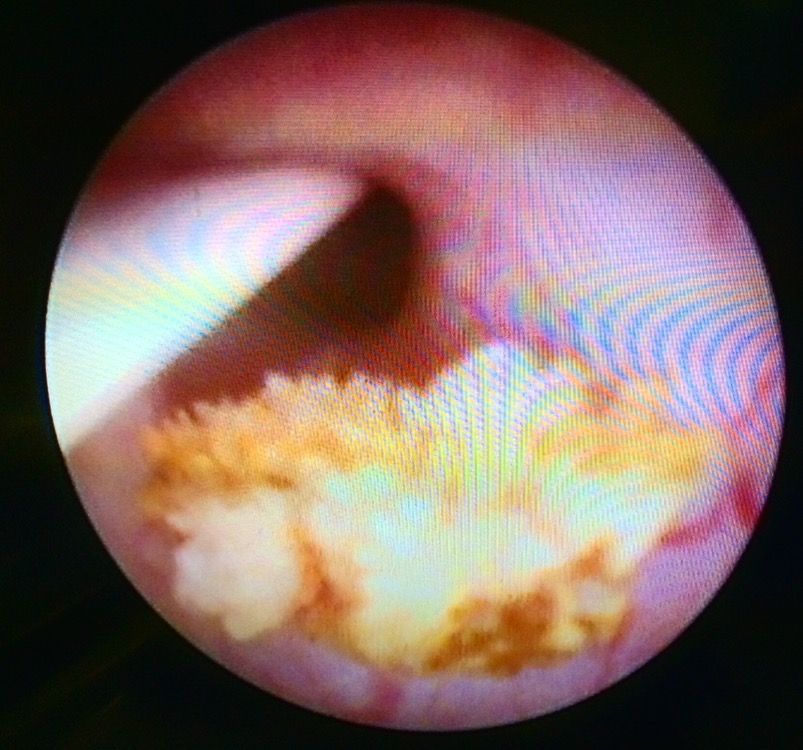

Cirugía de cálculo ureteral

Es un procedimiento que se hace por medio de endoscopia (ureteroscopia) de la via urinaria, en donde se entra al ureter a través de la vejiga, se llega hasta el sitio donde se encuentra el calculo o líto urinario que esta obstruyendo parcial o totalmente la luz del uretero. Con instrumentos muy delgados se fragmenta el líto con rayo laser y sus arenillas o fragmentos son extraidos por medio de una canastilla especial. una vez extraido el calculo su medico valorara la colocación de un cateter doble J, con la finalidad de mantener abierto el consucto del ureter durante un par de semanas y posterior a ello se retira el cateter. Existen otras técnicas de tratamiento, cada caso debe personalizado.